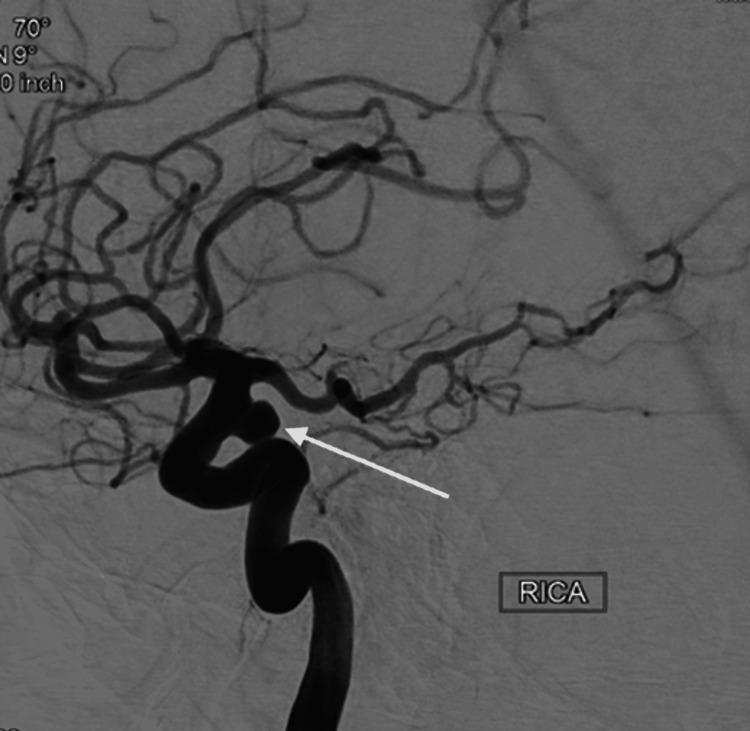

Ruptured cerebral aneurysms can cause significant morbidity and mortality. Endoluminal devices to treat aneurysms such as the Pipeline™ Flex Embolization Device with Shield Technology (PFES) (Medtronic, Dublin, Ireland) integrate phosphorylcholine on the surface of the device in order to reduce platelet adherence that causes periprocedural thromboembolic events and subsequent long-term intrastent stenosis. In addition to the Shield Technology, patients are commonly placed on dual antiplatelet therapy (DAPT) for six months to reduce thromboembolic events and subsequent long-term intrastent stenosis. There is a strong positive correlation between the length of DAPT use and bleeding. Here, we present a case of a 66-year-old female with a right supraclinoid internal carotid artery (ICA) aneurysm treated with a PFES who was placed on dual antiplatelet therapy for the first 31 days postoperative and subsequently maintained on aspirin (ASA) 81 mg monotherapy. At two months, a follow-up diagnostic cerebral angiogram showed complete occlusion of the aneurysm with a patent stent. Our case sets the stage for further research into the optimal length of dual antiplatelet therapy required in PFES to prevent short and long-term thromboembolic events. This report indicates that it may be safe for patients with PFES to intermittently halt the use of DAPT to manage bleeding complications or perform surgery.

破裂的脑动脉瘤可导致严重的发病率和死亡率。用于治疗动脉瘤的腔内装置,如带有护盾技术的Pipeline™ Flex栓塞装置(PFES)(美敦力公司,爱尔兰都柏林),在装置表面整合了磷酸胆碱,以减少导致围手术期血栓栓塞事件和随后长期支架内狭窄的血小板粘附。除了护盾技术外,患者通常还需接受六个月的双联抗血小板治疗(DAPT),以减少血栓栓塞事件和随后的长期支架内狭窄。DAPT使用时间长短与出血之间存在很强的正相关性。在此,我们报告一例66岁女性,其右侧床突上段颈内动脉(ICA)动脉瘤采用PFES治疗,术后前31天接受双联抗血小板治疗,随后维持阿司匹林(ASA)81mg单药治疗。两个月时,随访诊断性脑血管造影显示动脉瘤完全闭塞,支架通畅。我们的病例为进一步研究PFES预防短期和长期血栓栓塞事件所需的最佳双联抗血小板治疗时长奠定了基础。本报告表明,对于使用PFES的患者,间歇性停用DAPT以处理出血并发症或进行手术可能是安全的。